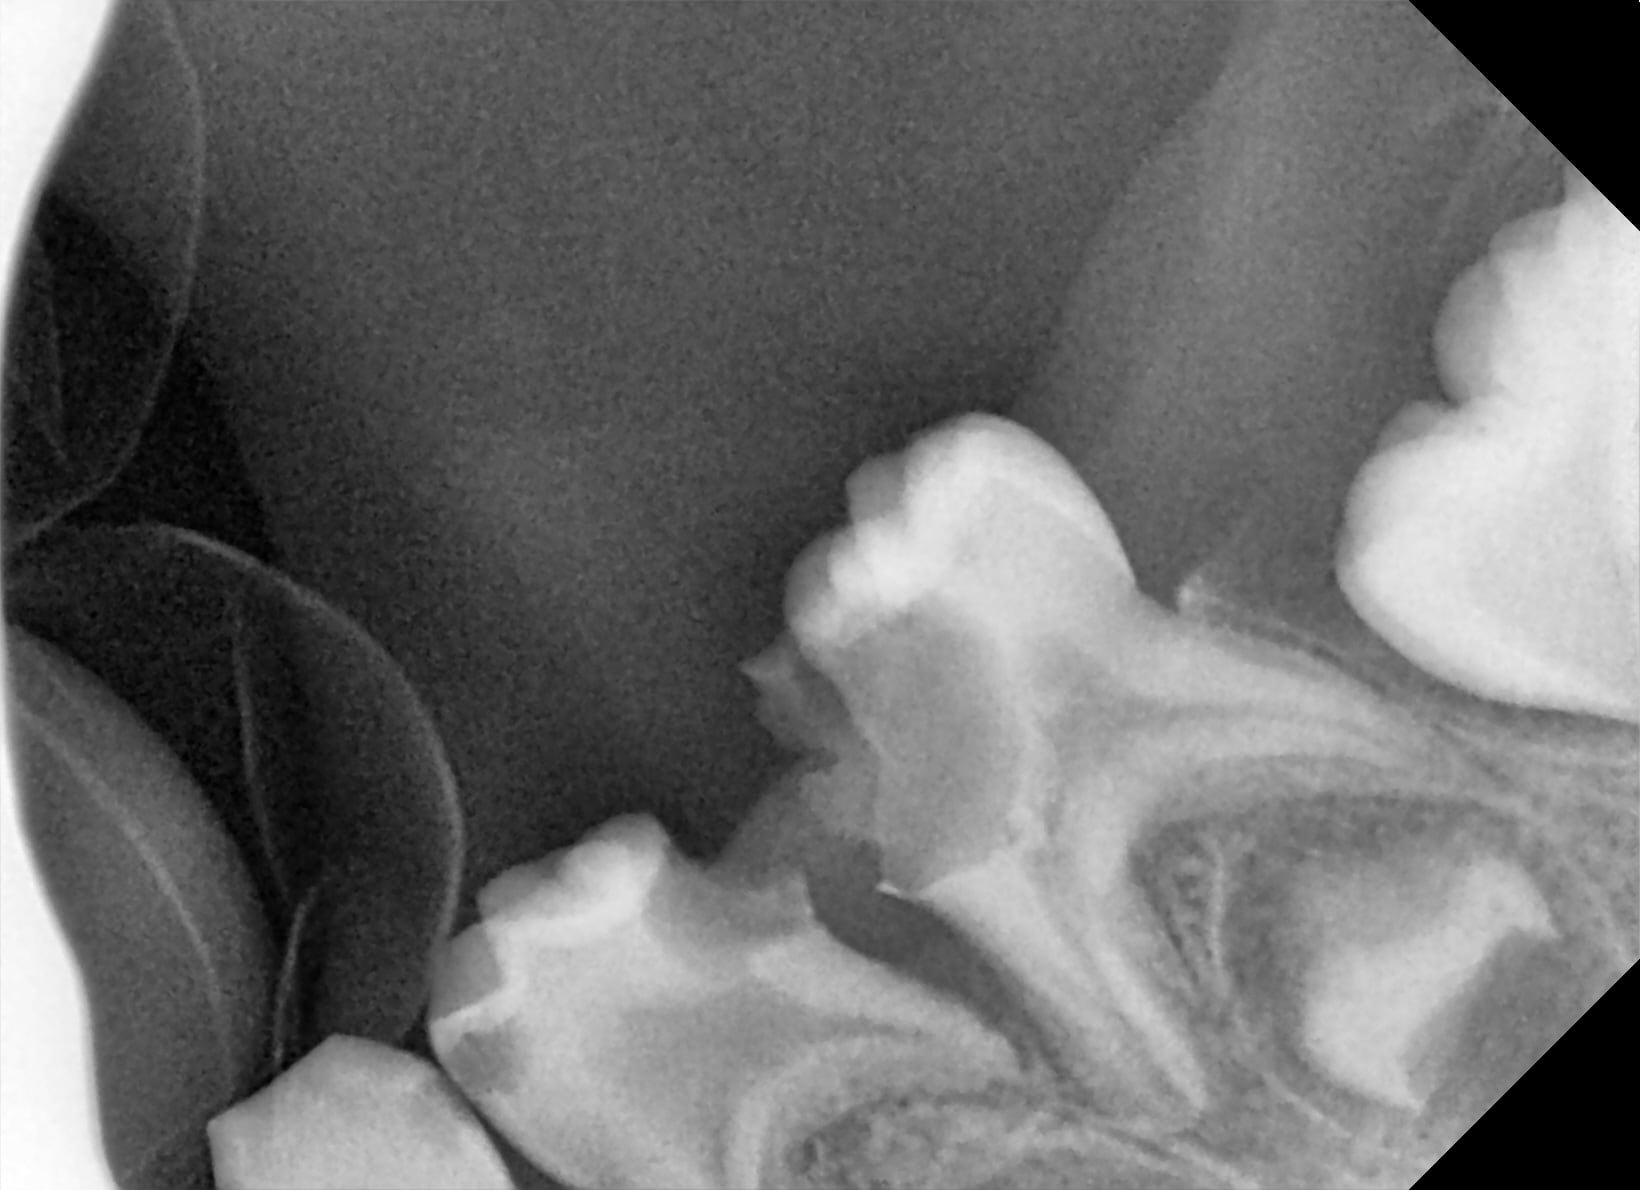

angulateur pedo en viande premier choix, mais à 4 ans c'est chaud.

pas de surprise pour le reste effectivement.

Je crois que la 63 est indemne..

en attendant je sais même pas si je vais la soigner la gamine. Je me suis chopper une suée pour faire deux pauvre obturation qui seront à refaire..